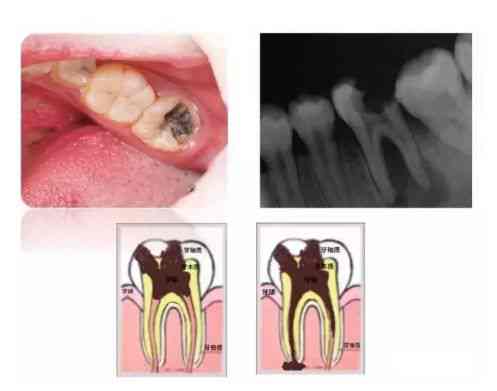

我们的牙齿跟木头一样,年久失修不注意保养就会蛀掉。看下面的牙齿,黑色和黄色的部分就是蛀坏的部分。

当牙釉质持续的破坏腐蚀后,就会慢慢形成浅表的破坏。浅龋可能是黑色的窝沟或者很小的龋洞,也可以仅仅表现为白色的斑块。这个时候因为牙齿破坏小并且没有明显的症状往往很难引起人们的注意。然后龋洞逐渐扩大,进入到牙本质形成较大的龋洞,这时食物会卡在洞里面,有可能吃点甜食就会酸痛。再往下发展达到牙本质深层形成深龋时,症状就更明显了,冷热刺激时都会感到疼痛。像图中这颗牙破坏的范围很广,整个牙齿表面都变黑了。